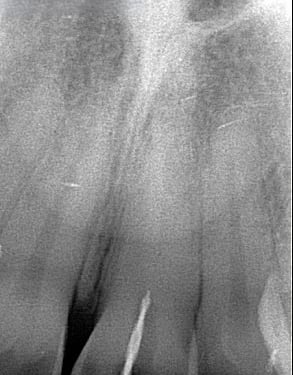

Reabsorción Externa

La reabsorción externa es la pérdida de tejido dental desde el exterior del diente hacia adentro, a menudo como resultado de un trauma o infección.

Los pacientes pueden no tener síntomas hasta que el diente se afloje.

El tratamiento incluye la eliminación de la causa y, a veces, un tratamiento de conducto. En casos severos, puede ser necesario extraer el diente.